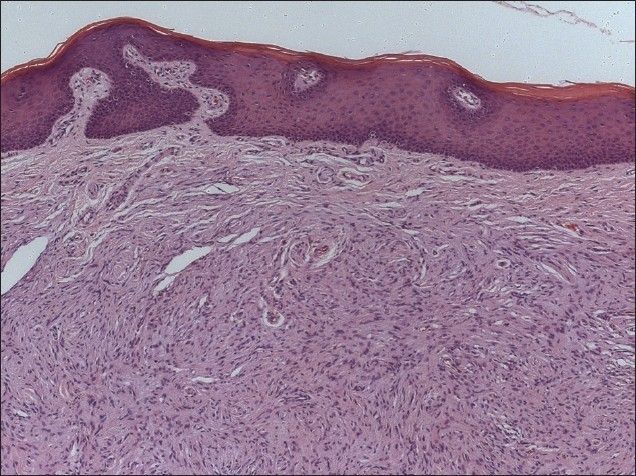

Histopathological investigation revealed that the tumor was composed of interlacing bundles of elongated cells with wavy nuclei and small nerve fibers. These cells are bland and disorderly with intracellular collagen strands [Figures 2 and 3]. Immunohistopathologic assessment showed cells positive for S-100 [Figures 4 and 5]. Pathological diagnosis was a NF with no signs of malignancy. There were no signs of recurrence at the 1-year follow-up visit [Figure 6].

Figure 2.

Panoramic view of the histological findings (H and E, ×10)

Figure 3.

Detailed appearance of the lesion. Interlacing bundles of spindle cells with hyperchromatic nuclei (H and E, ×40)

Histopathologically, the NF exhibits an irregular pattern with interlacing bundles of spindle-shaped cells with round or fusiform nuclei, and eosinophilic cytoplasm within a loose matrix of fine fibrillary collagen.[5,6,8] It is unencapsulated and composed of mixture of Schwann, perineural-like and fibroblastic cell.[8] Also, NF is immunopositive for S-100 protein, indicating its neural origin.[10] A thorough histopathological analysis supported by immunohistochemistry is essential for the correct diagnosis of these oral soft tissue growths.[10,15]